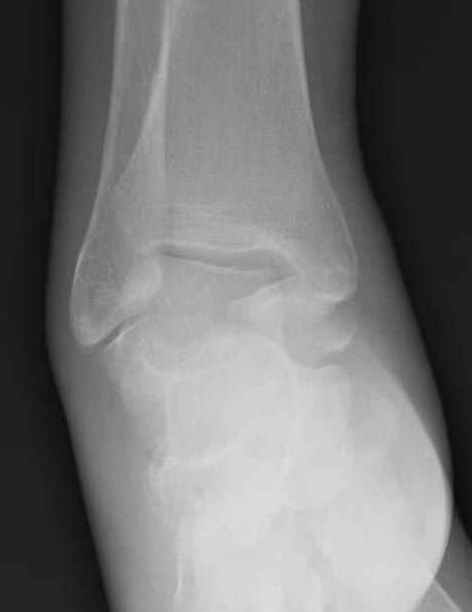

Уважаемые участники русского Ортофорума, поздравляю всех со всеми прошедшими праздниками: Новым годом, Рождеством, Hanukkah, Kwanzaa, желаю участникам всего наилучшего и здоровья.Повреждение таранной кости.Больной 81г автоавария, повреждение таранной кости, здесь снимки.

Вдогонку по поводу перелома таранной кости, больная 81, не страдает диабетом, перелом закрытый, в первый же день поступления ограничились временным наружным фиксатором (как на снимке).

Примеры на снимке...